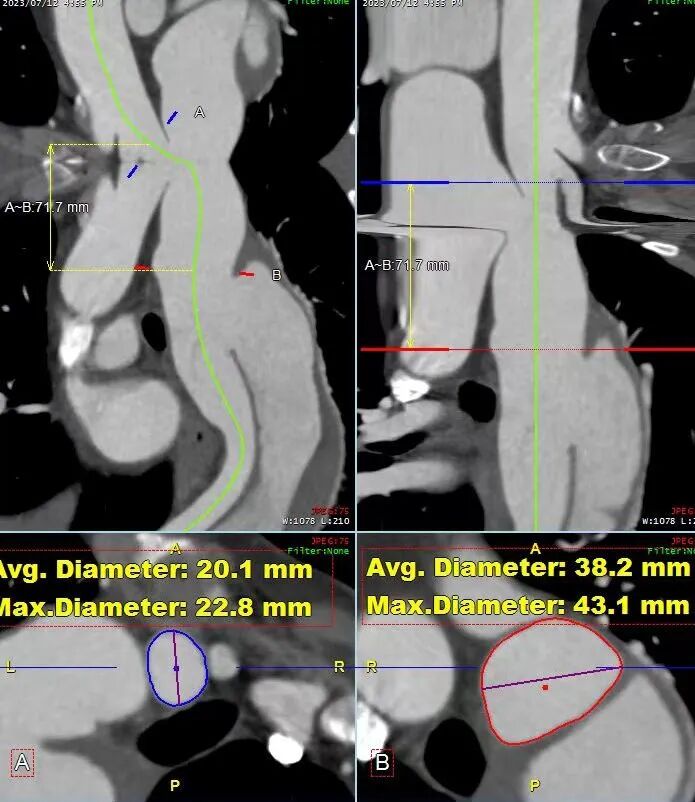

术前CTA评估与测量

术前CTA提示主动脉夹层(Stanford B型,Debake llI型),主动脉弓及降主动脉瘤样扩张,累及左锁骨下动脉起始段,管径最粗约7.4cm,夹层初破口位于降主动脉起始段,向下累及至腹主动脉(约平胸12椎体水平),真腔小,假腔大,腹腔干发自混合腔,肠系膜上动脉、下动脉,双肾动脉均起自真腔,双肾灌注未见差异。

gore医疗怎么样「胸有乾坤」可调可控 精准出击——四川大学华西医院肖正华教授团队:CADS治疗B型主动脉夹层病例分享_https://www.jmylbn.com_新闻资讯_第6张

术前三维重建

术前CTA详解:

病例特点

1. 弓型陡峭,成角;

2. 自左颈总后缘小弯侧锚定区不足1cm;

3. 巨大破口,约33mm,病变累及至腹腔干平面。